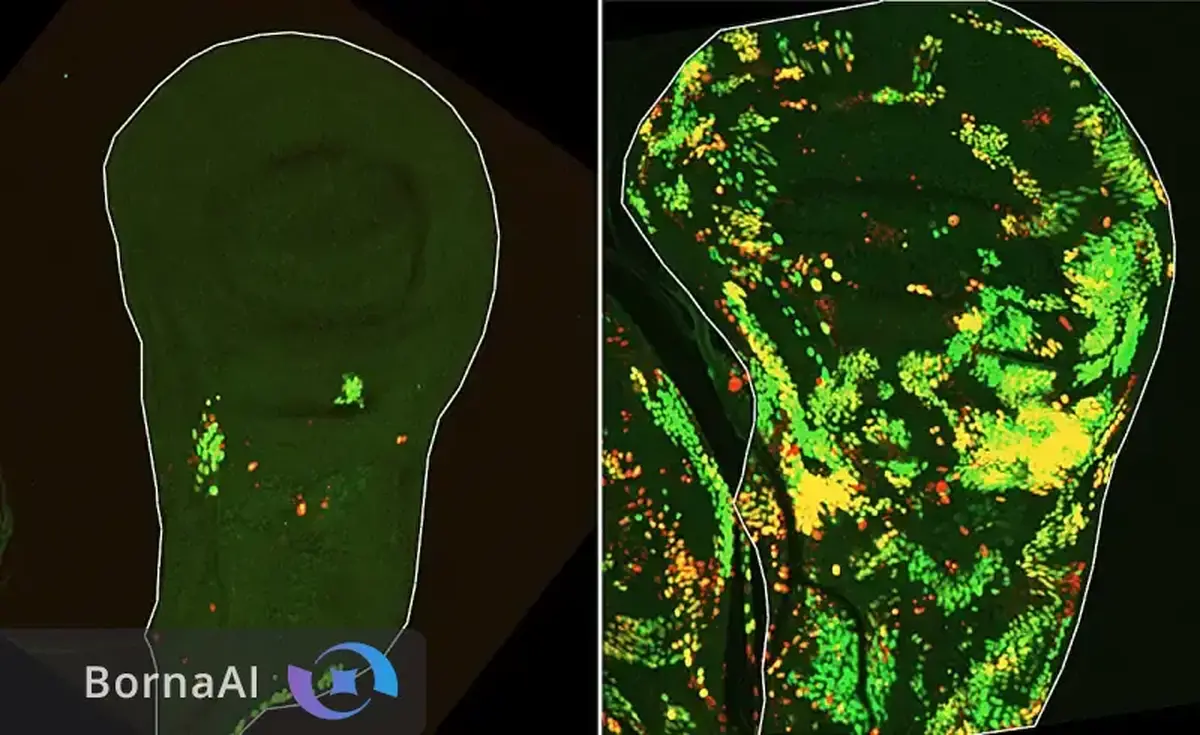

در ناحیه هیپوکامپ که نقش کلیدی در حافظه دارد، بافت مغز فرد مبتلا به آلزایمر کاهش چشمگیر ارتباطات الیافی را نشان داد. مسیرهای حیاتی انتقال اطلاعات حافظه بهویژه مسیر پرفورانت تقریبا از بین رفته بودند؛ در حالی که هیپوکامپ سالم شبکهای متراکم و پیوسته از الیاف را نمایش میداد. این تصاویر امکان مشاهده مستقیم تخریب مدارهای حافظه را فراهم میکند. جالب آنکه تیم پژوهشی حتی یک نمونه مغزی مربوط به سال ۱۹۰۴ را نیز بررسی کرد و با وجود قدمت بیش از یک قرن مسیرهای پیچیده الیافی در آن قابل شناسایی بود.